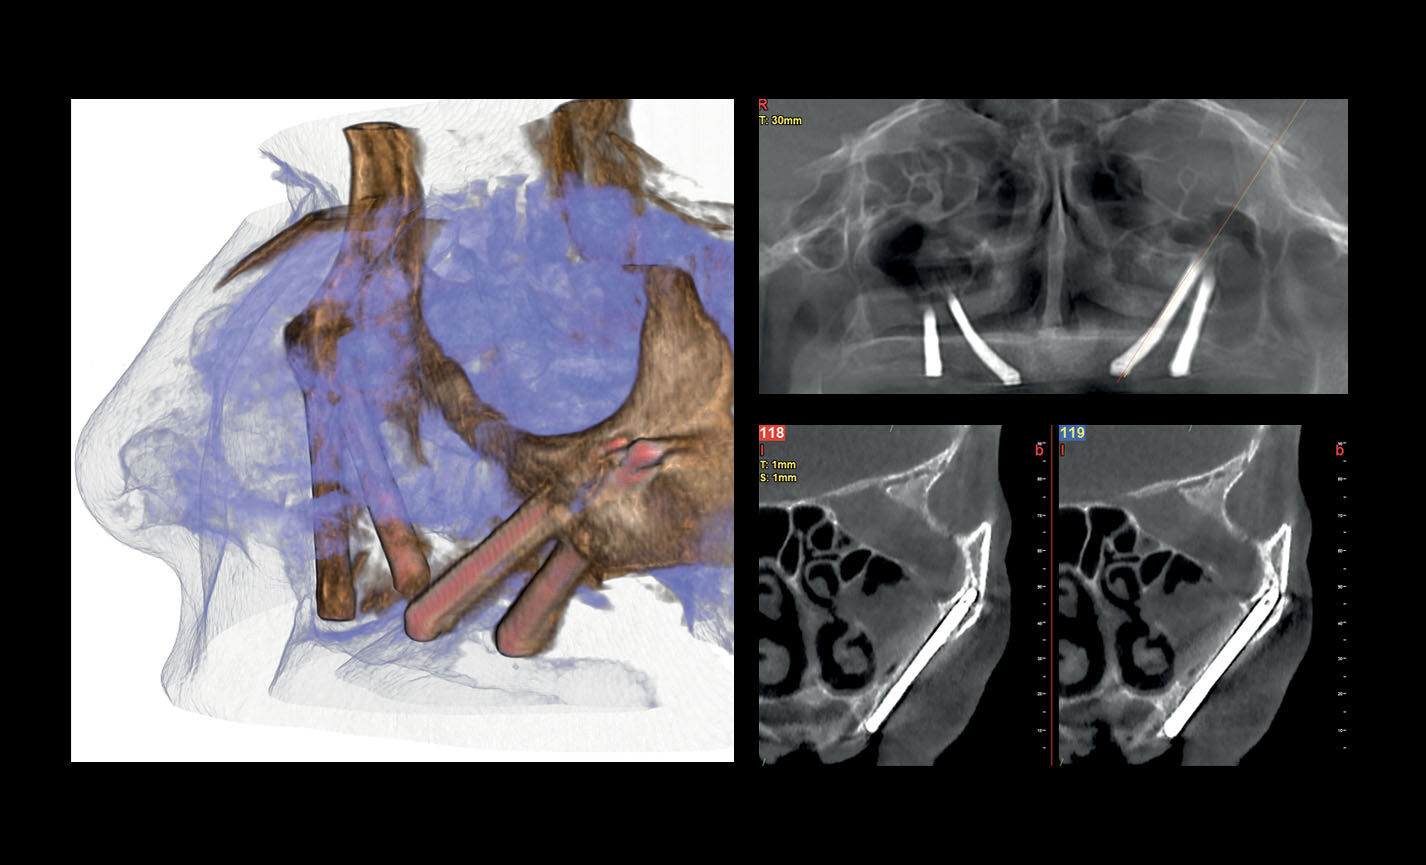

Évaluation des implants zygomatiques

Les volumes avec FOV 13 x 8 cm, ou 13 x 10 cm, représentent l’outil idéal pour la planification des implants zygomatiques. En effet, le diamètre de 13 cm est le seul qui permet d’inclure tout le zygoma dans le balayage, sans coupes.